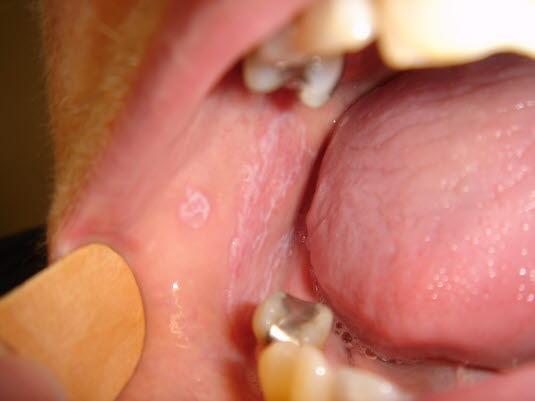

Lichen planus eller lichen ruber planus er en vanlig forekommende, langvarig og ofte sterkt kløende hudlidelse som i det tidlige forløpet er preget av små, kantete, flate hudforandringer. Hos 25-35 prosent angripes også slimhinner, og dette viser seg hyppigst på innsiden av kinnene der det kan ses hvite flekker og striper (se lichen planus i munnhulen). Typiske steder med hudforandringer er underarmenes håndflateside, lår, legger og området rundt halebeinet/baken.

Lichen planus munnKarakteristiske trekk ved slimhinneforandringer:

- Hvite flekker og striper som kan utvikle seg til områder med sårdannelse